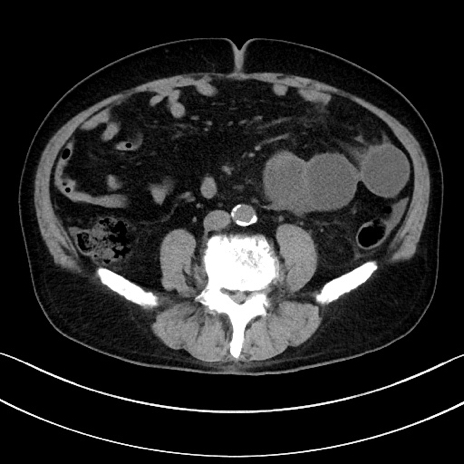

症例15(横断像)

【症例】70歳代男性

【主訴】腹痛

【現病歴】今朝から腹痛あり。全体的に痛い。特に左上の方。排ガスが今日はない。冷や汗が出る。

【既往歴】直腸癌術後

【身体所見】左側腹部〜上腹部に圧痛あり。腹膜刺激症状明らかなではない。軽度反跳痛。左下腹部に術後瘢痕あり。

【データ】WBC 7700、CRP 0.02